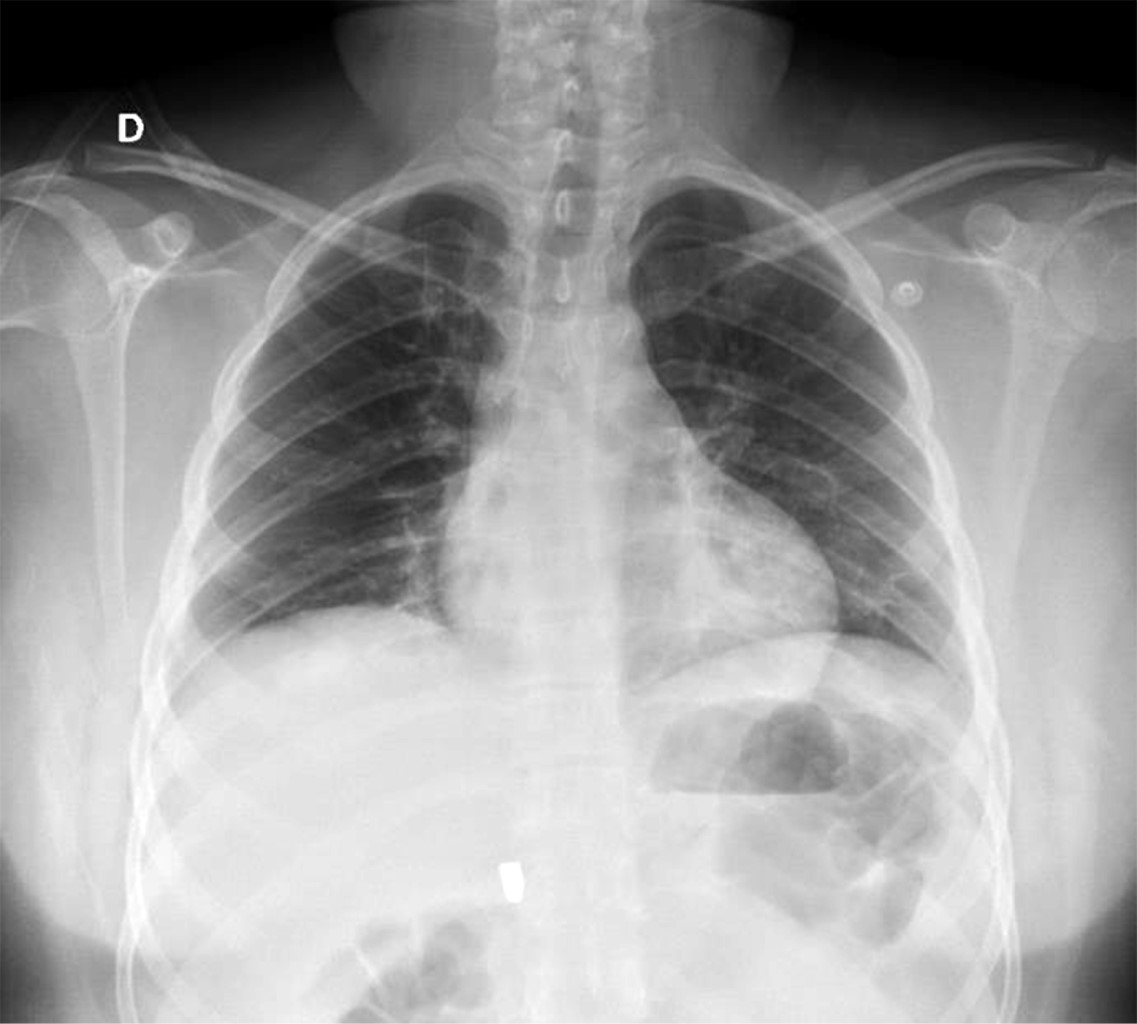

En la exploración física, sus signos vitales fueron los siguientes: frecuencia cardiaca: 74 latidos/minuto; tensión arterial: 98/67 mmHg; frecuencia respiratoria: 19/minuto, temperatura de 36 °C y saturación de oxígeno: 98%. En tórax presentaba un orificio de entrada de PAF en el cuadrante superior externo de la mama derecha (Figura 1), los campos pulmonares estaban bien ventilados. El abdomen era plano, con peristalsis, blando y sin dolor a la palpación. La biometría hemática reportó lo siguiente: hemoglobina: 12.8 g/dl, hematocrito 36.4% y leucocitos: 6,400/ml. La radiografía de tórax descartó neumotórax (Figura 2). Una TC de tórax y abdomen mostró un cuerpo extraño metálico alojado en la línea parasagital derecha a nivel de la doceava vértebra torácica (Figura 3), sin lesión pulmonar ni diafragmática (Figuras 4 y 5); en abdomen se observó un trayecto por PAF con lesión hepática grado IV de 12 cm por 2.3 cm en los segmentos IV, VII y VIII de Couinaud (Figura 5), líquido libre escaso, sin lesión de ningún otro órgano (Figuras 3, 5 y 6). Veinticuatro horas después se le realizó una TC de control, evidenciando la lesión hepática sin colección subcapsular ni extravasación activa a la aplicación del medio de contraste, sin aumento del líquido libre. Ante la correlación de estos hallazgos con la estabilidad clínica, se egresó a la paciente al cuarto día de su ingreso. Sin complicaciones un mes después de su alta.

Figura 2